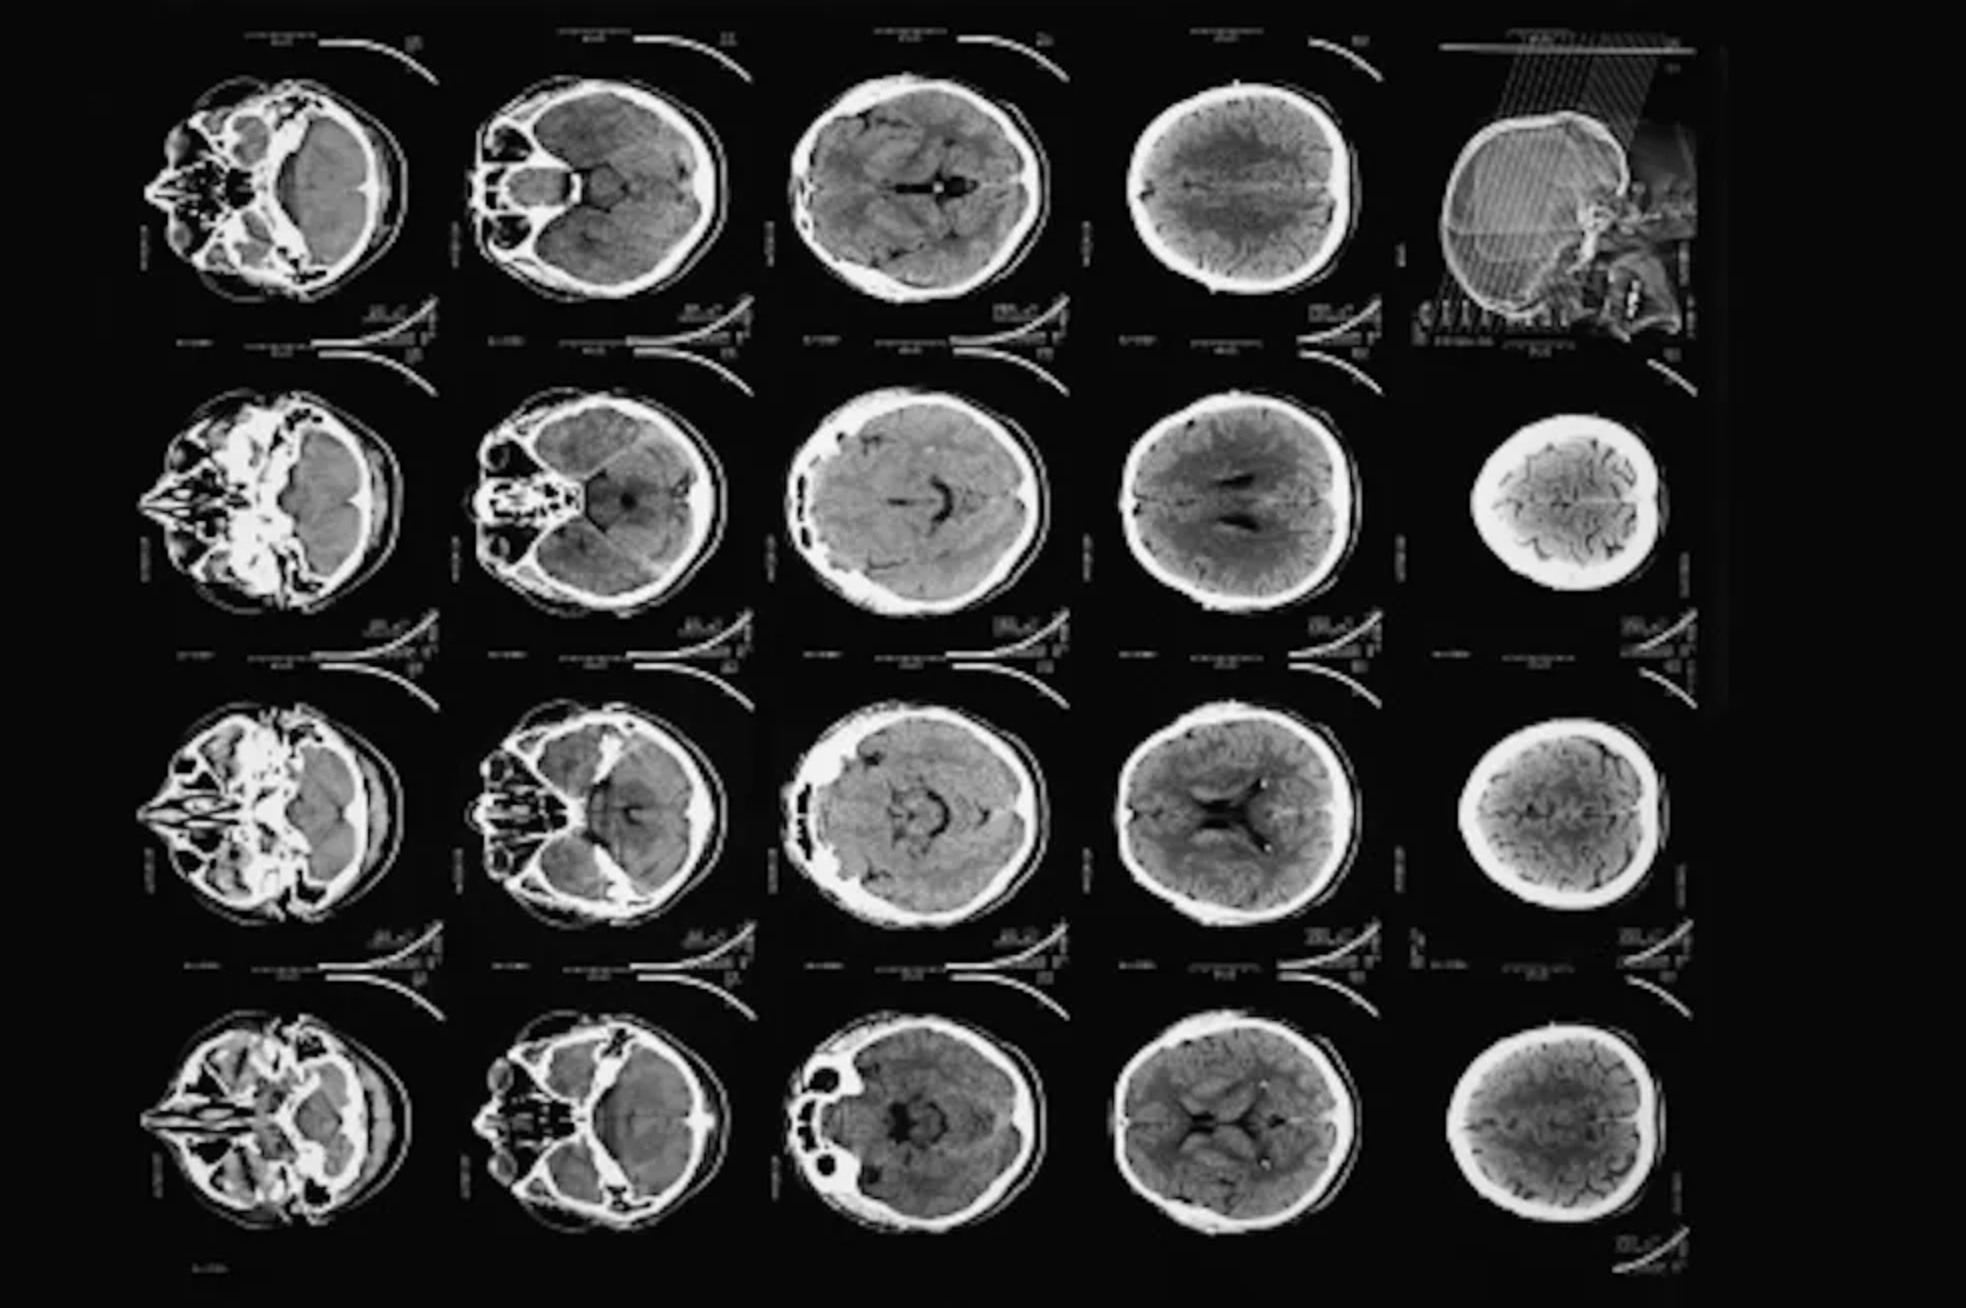

The first computed tomography image – a CT scan – of the human brain was made 50 years ago, on Oct. 1, 1971. Hounsfield never made it to Egypt, but his invention did take him to Stockholm and Buckingham Palace.

First, he would conceptually divide the brain into consecutive slices – like a loaf of bread. Then he planned to beam a series of X-rays through each layer, repeating this for each degree of a half-circle. The strength of each beam would be captured on the opposite side of the brain – with stronger beams indicating they’d traveled through less dense material.

Finally, in possibly his most ingenious invention, Hounsfield created an algorithm to reconstruct an image of the brain based on all these layers. By working backward and using one of the era’s fastest new computers, he could calculate the value for each little box of each brain layer. Eureka!

It was not a fast process – 30 minutes for the scan, a drive across town with the magnetic tapes, 2.5 hours processing the data on an EMI mainframe computer and capturing the image with a Polaroid camera before racing back to the hospital.

And there it was – in her left frontal lobe – a cystic mass about the size of a plum. With that, every other method of imaging the brain was obsolete.

By 2020, technicians were performing more than 80 million scans annually in the U.S.. Some physicians argue that number is excessive and maybe a third are unnecessary. While that may be true, the CT scan has benefited the health of many patients around the world, helping identify tumors and determine if surgery is needed. They’re particularly useful for a quick search for internal injuries after accidents in the ER.